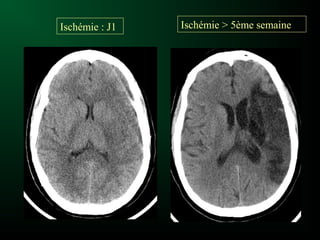

Ischémie cérébrale et Scanner

Ischémie : J1 Ischémie > 5ème semaine

Ischémie cérébrale etScanner Signes précoces: Sémiologie de l’œdème cytotoxique : – Hypodensité prédominant dans la substance grise – Dédifférenciation substance grise-substance blanche

Evolution de l’hypodensité –Scanner le plus souvent normal au début – Lésion visible après la 12ème heure – Hypodensité systématisée à un territoire artériel • Cortico-sous-corticale • Triangulaire, à base périphérique – S ’accentue franchement à partir de la 3ème semaine – Hypodensité liquidienne séquellaire avec signes d ’atrophie cérébrale localisée à partir de la 5ème semaine Ischémie cérébrale et Scanner

Ischémie : J1Ischémie > 5ème semaine